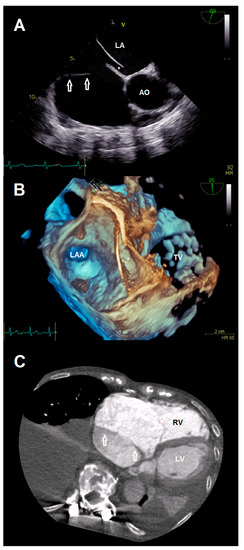

A 78-year-old female patient presented at the emergency department due to progressive dyspnea and a weight gain of 15 kg in recent weeks. Physical examination revealed massive peripheral edema and concomitant congestive dermatitis, but no jugular vein distention. Laboratory results were suggestive for diagnosis of cardiac decompensation with N-terminal pro-brain natriuretic peptide (NT-proBNP) plasma levels of 2320 ng/L, while renal function and inflammation parameters were unremarkable. As the patient was already known to have severe TR with last heart failure hospitalization one year ago, she was admitted for cardiac recompensation and evaluation of tricuspid valve intervention. Further notable medical history included permanent atrial fibrillation, iron deficiency anemia, and severe osteoporosis with previous spondylodesis and extensive oral pain therapy. Echocardiographic examination confirmed progression to massive TR (Vena contracta: 15 mm, effective regurgitation orifice area: 0.9 cm²), but also revealed an additional right atrial membrane ranging from the interatrial septum to the ostium of the IVC consistent with a CTD (Figure 1, Videos S1–S8). Application of contrast medium, as part of the bubble study, yielded an additional patent foramen ovale (PFO, Figure 2A,B; Videos S9 and S10). Besides, both atria (left atrial volume index, 109 mL/m2; right atrial volume index, 189 mL/m2), the right ventricle (right ventricular end diastolic diameter, 51 mm), and the IVC (33 mm) were severely dilated, whereas the left ventricular end diastolic diameter (46 mm) was in normal range. Right ventricular (tricuspid annular plane systolic excursion (TAPSE), 23 mm) and left ventricular function (ejection fraction, 60%) were preserved. Furthermore, liver vein congestion with flow reversal and incipient parenchymal liver disease, interpreted as cardiac cirrhosis, were identified underlining the significance of present TR (Figure 1E). Invasive coronary angiography excluded the presence of coronary artery disease, right-heart catheterization determined an isolated postcapillary hypertension (pulmonary artery pressure, 52/17/29 mmHg; wedge pressure, A-wave—20 mmHg, V-wave—23 mmHg, mean—19 mmHg). Cardiac computed tomography was conducted for the purpose of interventional planning (Figure 2C).

Jcdd 08 00111 g001

Figure 2. (A) Anatomical relationship between the additional membrane (arrows) and present patent foramen ovale (*). (B) 3-D view showing the patent foramen ovale (*). (C) Cardiac computed tomography visualizing the cor triatriatum dexter (arrows) for procedural planning. Abbreviations: AO, aorta; LA, left atrium; LAA, left atrial appendage; LV, left ventricle; RV, right ventricle; TV, tricuspid valve.